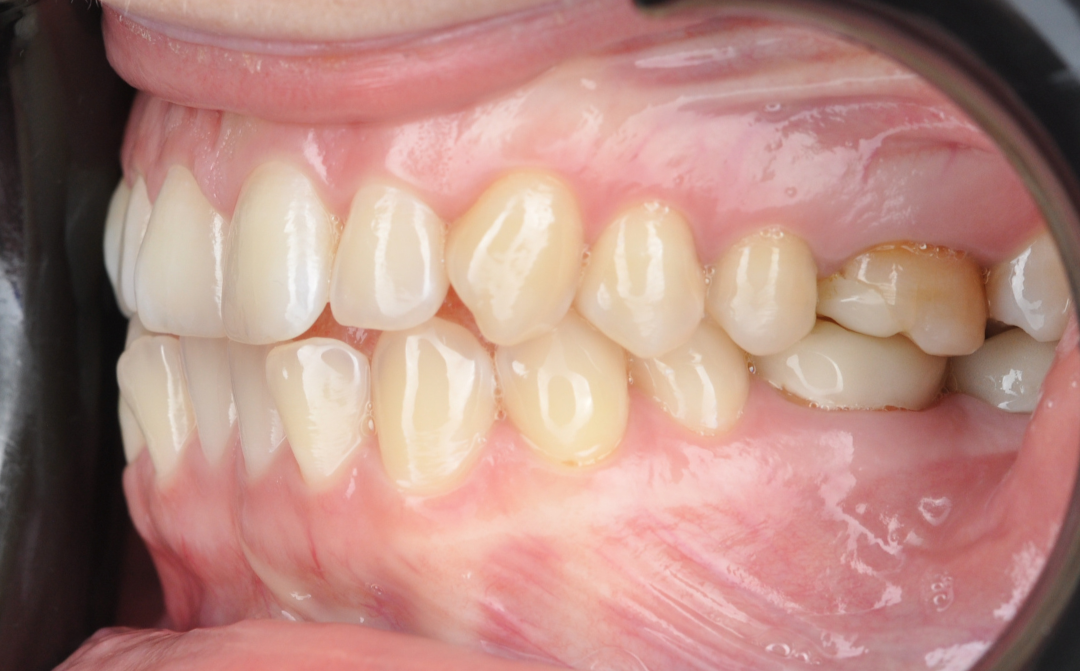

После

Этап №3

Ортодонтическая коррекция.

Стоматолог-ортодонт зафиксировал комбинированную брекет-систему (сверху керамические, а снизу – металлические брекеты).

- Исправление прямого прикуса (одной из частых причин дисфункции ВНЧС).

- Изменение положения зубов.

- Доведение контактов челюстей до физиологически правильного смыкания.

Финишная реставрация.

После снятия брекет-системы стоматолог-терапевт провела художественную реставрацию формы боковых резцов, добившись идеальной гармонии и естественности улыбки.